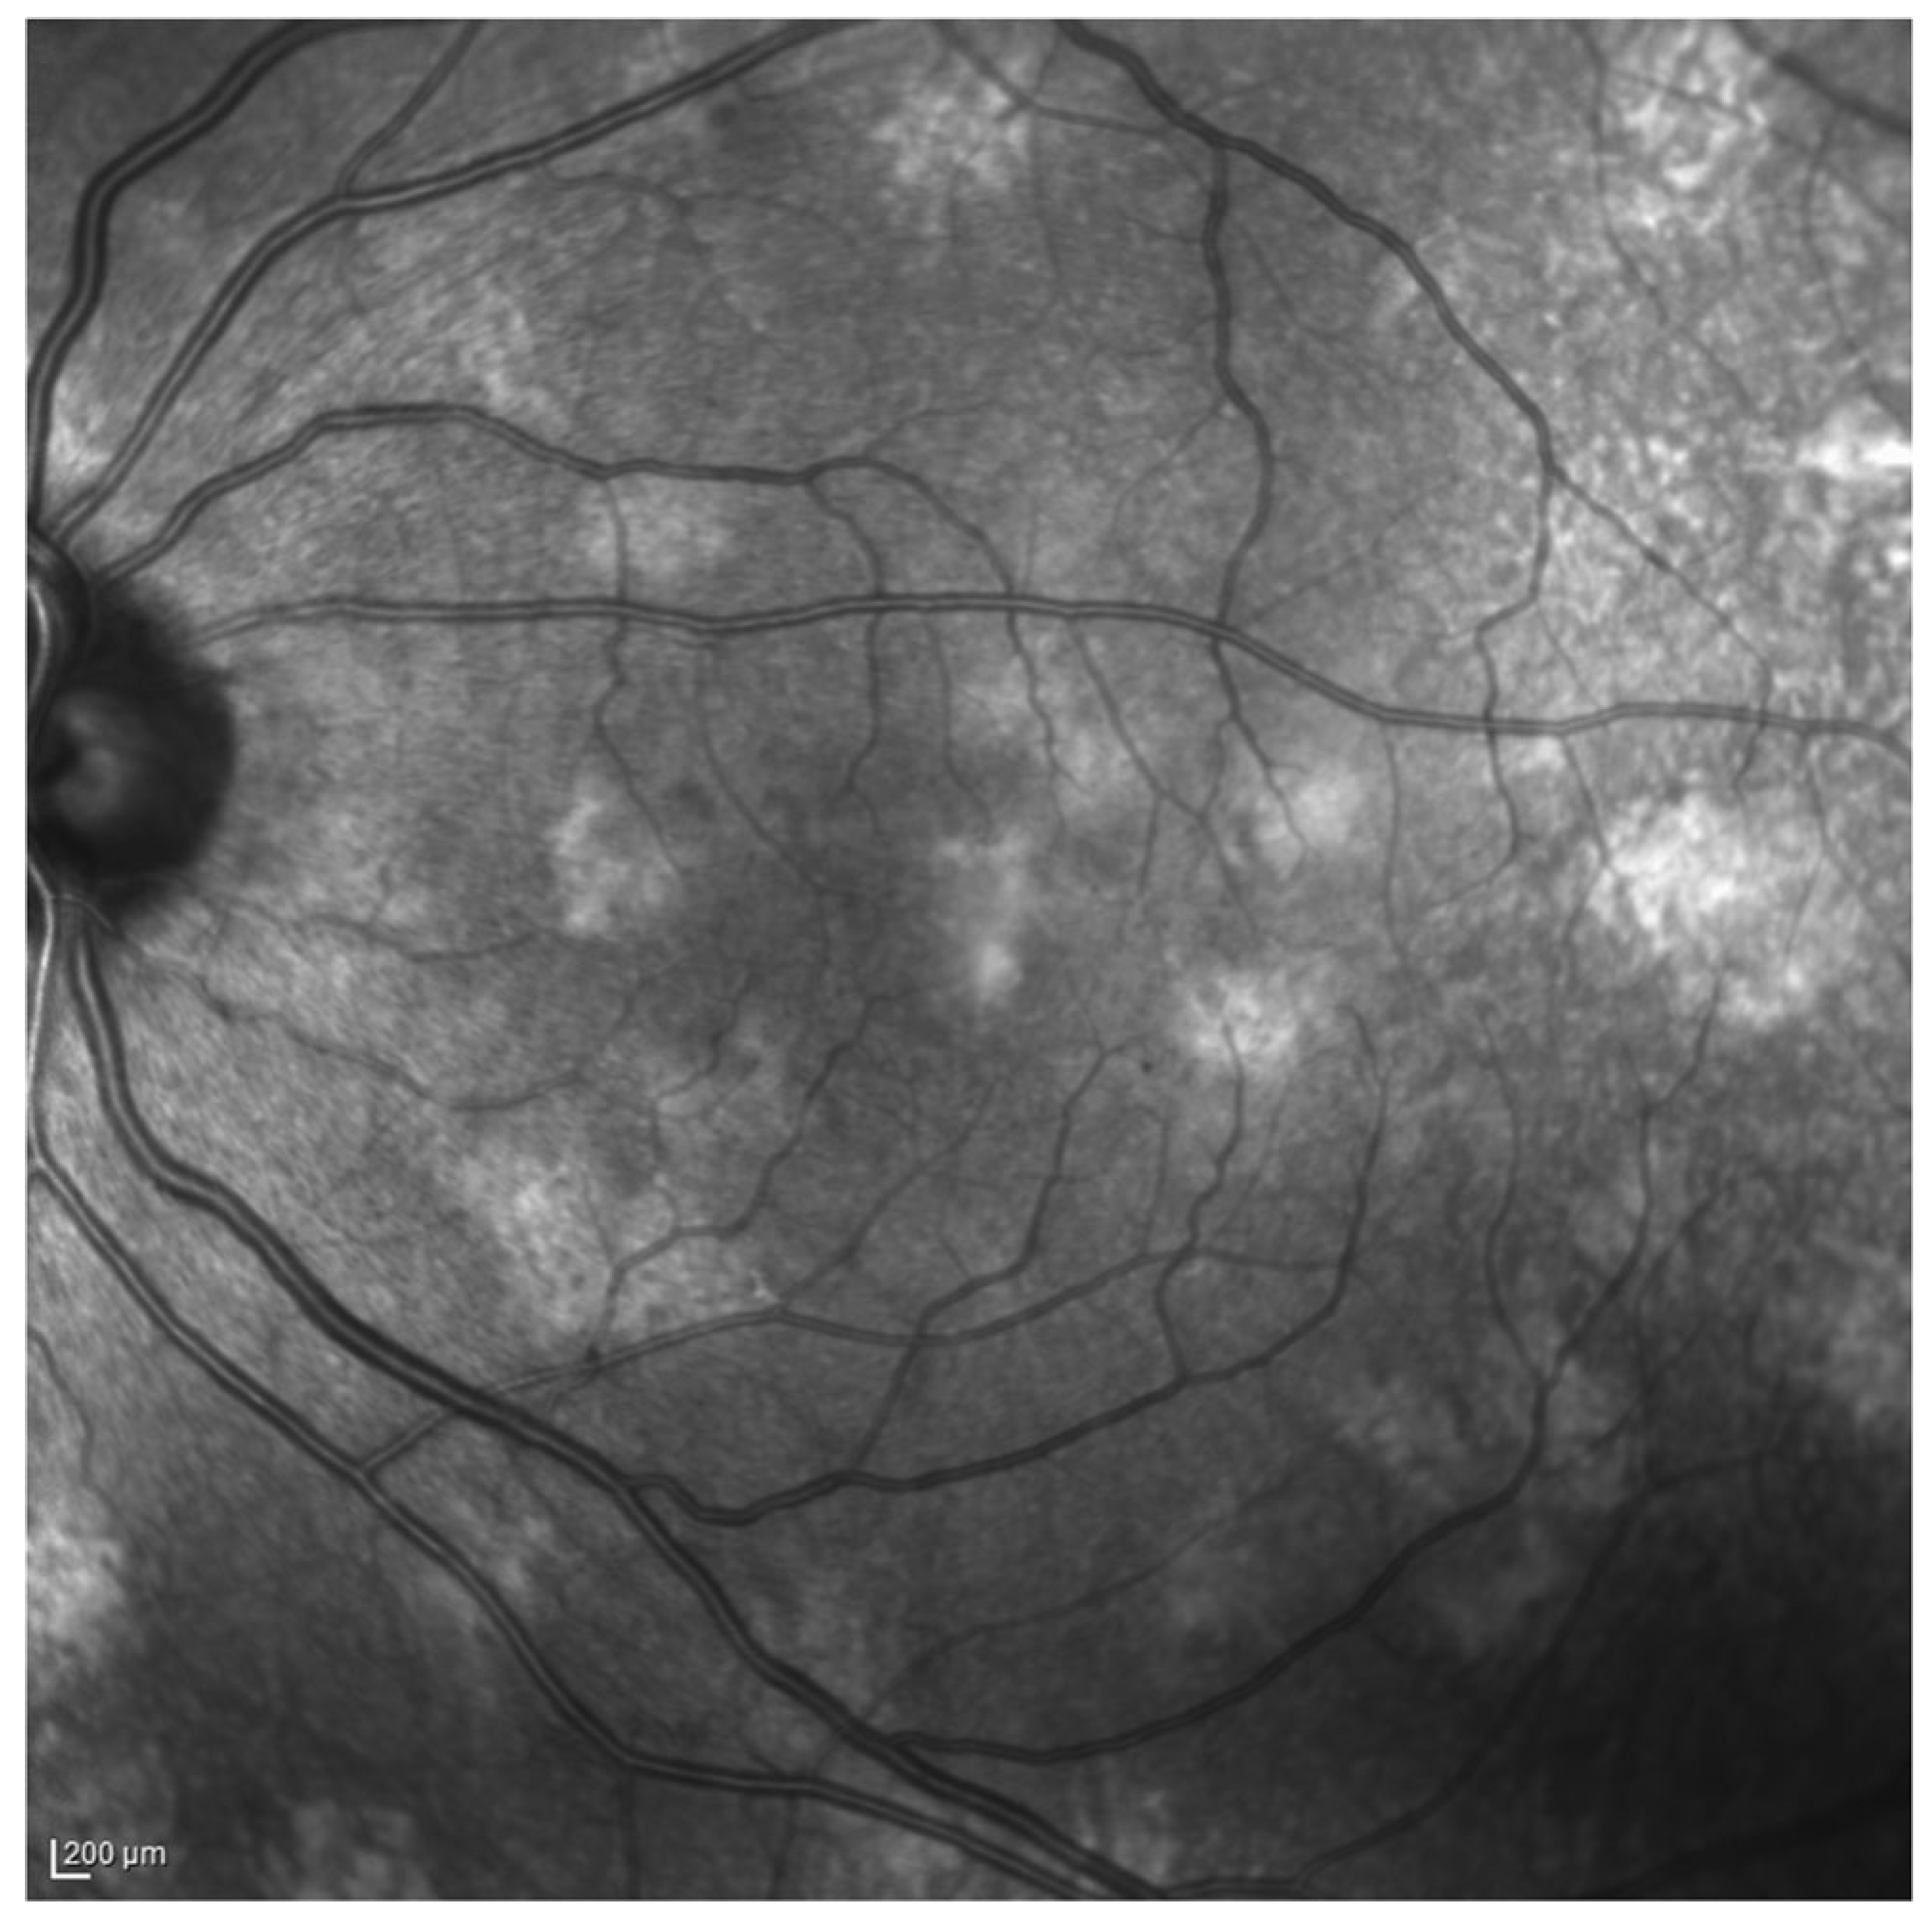

- Moramarco, A.; Giustini, S.; Nofroni, I.; Mallone, F.; Miraglia, E.; Iacovino, C.; Calvieri, S.; Lambiase, A. Near-infrared imaging: An in vivo, non-invasive diagnostic tool in neurofibromatosis type 1. Graefe’s Arch. Clin. Exp. Ophthalmol. 2018, 256, 307–311. [Google Scholar] [CrossRef]

- Viola, F.; Villani, E.; Natacci, F.; Selicorni, A.; Ophthalmology, G.M. Choroidal abnormalities detected by near-infrared reflectance imaging as a new diagnostic criterion for neurofibromatosis 1. Ophthalmology 2012, 119, 369–375. [Google Scholar] [CrossRef] [PubMed]

- Vagge, A.; Camicione, P.; Capris, C.; Sburlati, C.; Panarello, S.; Calevo, M.G.; Traverso, C.E.; Capris, P. Choroidal abnormalities in neurofibromatosis type 1 detected by near-infrared reflectance imaging in paediatric population. Acta Ophthalmol. 2015, 93, e667–e671. [Google Scholar] [CrossRef] [PubMed]